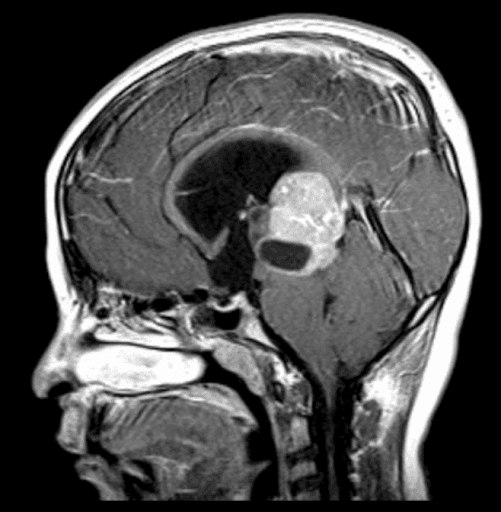

Figure 1: MRI of brain with pineal germinoma, sagittal view

TREATMENT PLAN: Bilateral papilledema in the presence of Parinaud syndrome is highly suggestive of a lesion of the dorsal midbrain. This patient was referred for imaging STAT. MRI confirmed a mass of the midbrain. Craniotomy was performed to place a shunt in order to relieve excess cerebrospinal fluid. The mass was found to be a germinoma of the pineal gland and was positive for cancer. Aggressive treatment of the cancer will include chemotherapy followed by radiation.

IMPACT ON PATIENT’S LIFE: The location of the tumor was causing obstructive hydrocephalus which can be fatal. By making the appropriate diagnosis and swiftly putting the plan into action, a life was saved. Furthermore, cancer was detected and may be appropriately treated.